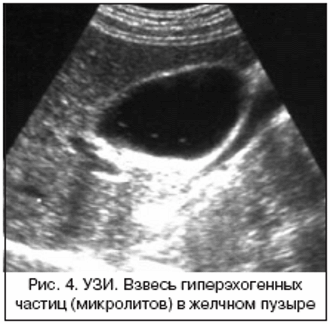

При ультразвуковом исследовании желчного пузыря часто в его полости обнаруживается взвесь. Взвесь является загустевшей желчью или субстанцией, состоящей из кристаллов холестерина, билирубиносодержащих пигментов, солей кальция.

- микролитиаз, состоящий из 4-5-милимметровых инородных тел, обнаруживающихся в процессе смены положения тела;

Билиарный сладж на УЗИ